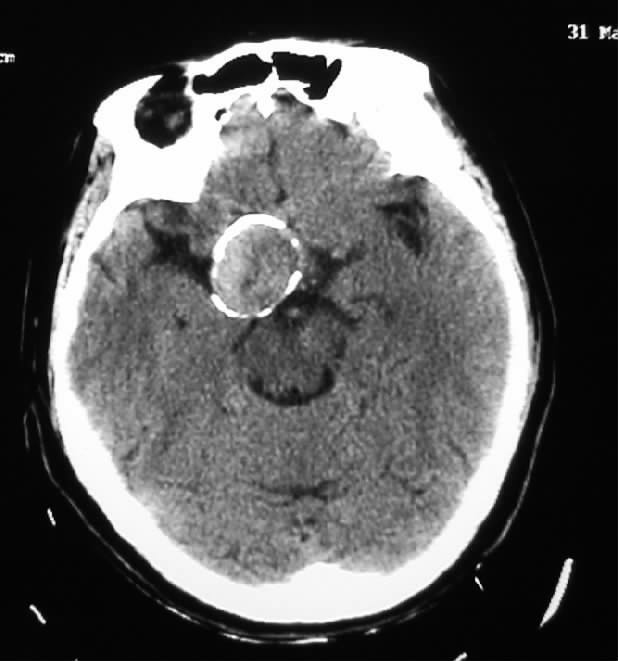

西京医院成功夹闭一例瘤壁钙化颅内巨大动脉瘤

多图|颅内动脉瘤的影像学诊断